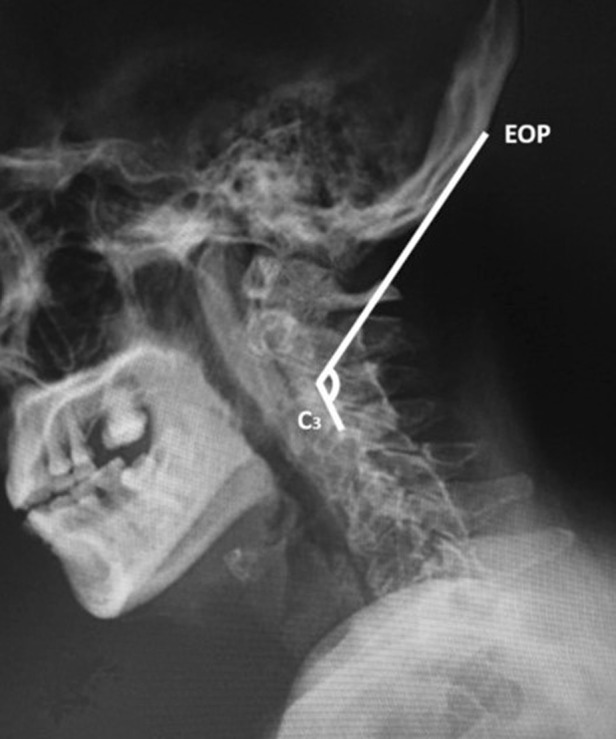

Fig. 6.

The measurement of the occiput-C3 angle was defined as the angle formed by the line drawn from the external occipital protuberance (EOP) to the tip of superior aspect of the posterior vertebral body of C3 intersection to the line drawn from the posterior aspect of the C3 vertebral body